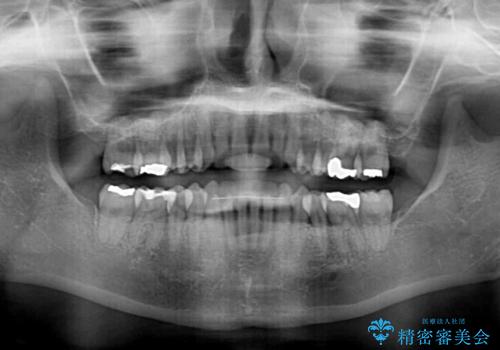

- 下顎の八重歯と、上下のクロスバイトを気にして来院された患者様です。

インビザラインを用い、下顎全体の後方移動、IPR(歯と歯の間を削る)と歯列全体を拡大させることで、歯並びを整えていくこととしました。

奥に位置していた上の前歯が下の前歯を乗り越える際、奥歯でものを咬むことができず、辛い時期が続きました。